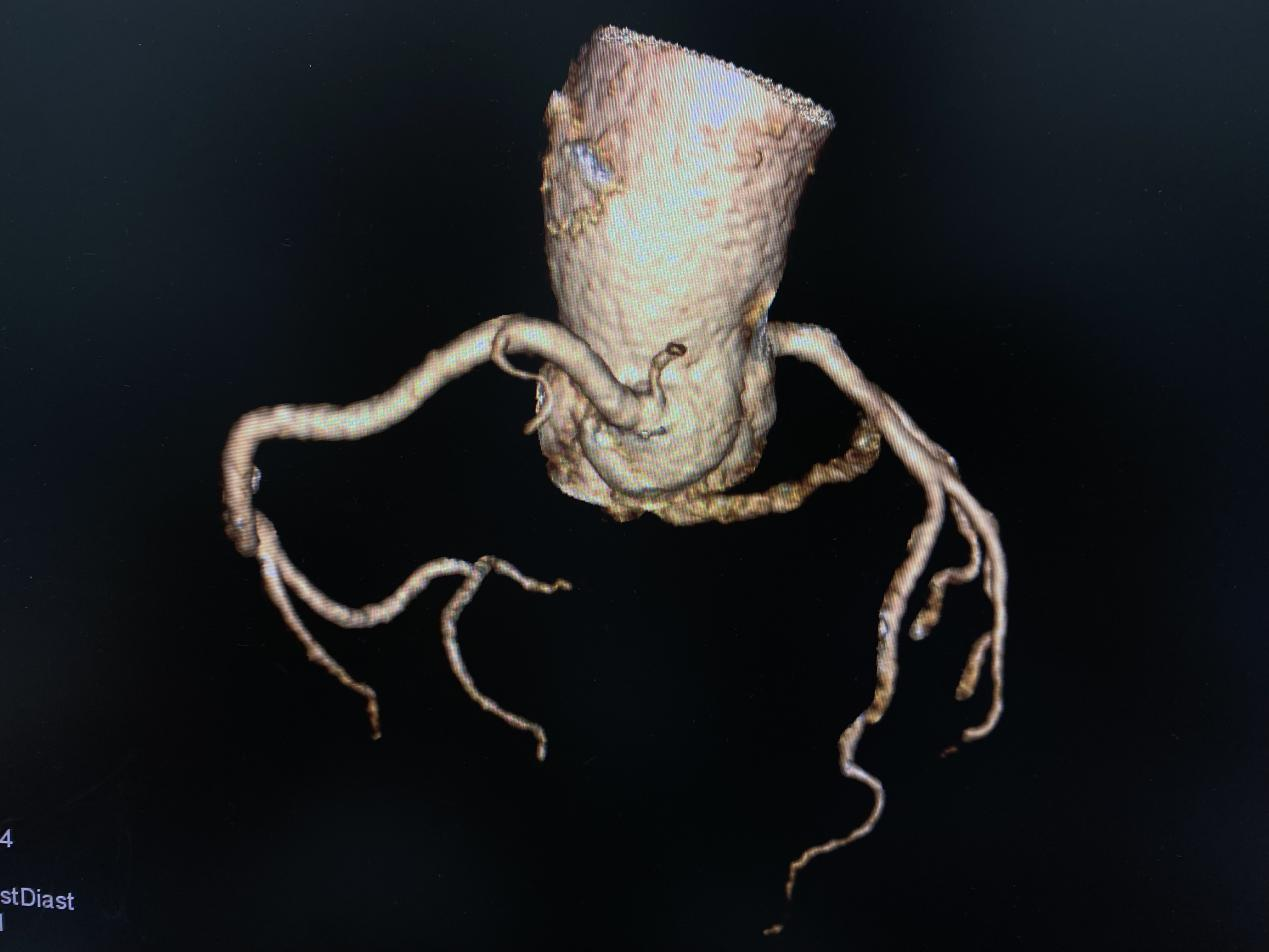

医学影像科在李涛、王鹏两位主任的积极领导下,先后开展全身各部位、多部位联合扫描及强化,CT增强扫描开展了冠状动脉CTA、肺动脉CTA、头颈部血管CTA、胸腹主动脉CTA、下肢动脉CTA等多项新技术、新项目。

影像技师张锐准确的选择好扫描条件,计算好造影剂剂量、注射速率等方案后进行规范扫描,扫描完成,各支血管显示清晰,完成处理后传输到报告系统。

冠脉树

完成检查后,两位主任对图像、报告进行综合评价及审核。各项流程顺利,项目开展完好,填补我院血管强化检查领域空白,为我院医学影像发展开启了新的篇章!